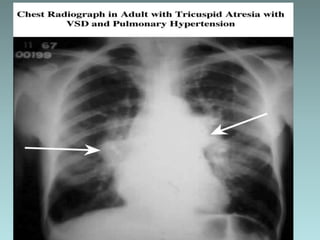

X-ray Studies

The heart size is normal or slightly increased, with

enlargement of the RA and LV. Pulmonary vascularity

decreases in most patients although it may increase in

infants with TGA.

Occasionally, the concave PA segment may produce a

boot-shaped heart, like the x-ray findings of TOF.

ELECTROCARDIOGRAPHY 1. “Superior” QRSaxis (between 0 and –90 degrees) is characteristic. It appears in most patients without TGA and in only 50% of patients with TGA. 2. LVH is usually present; RAH or biatrial hypertrophy (BAH) is common X-ray Studies The heart size is normal or slightly increased, with enlargement of the RA and LV. Pulmonary vascularity decreases in most patients although it may increase in infants with TGA. Occasionally, the concave PA segment may produce a boot-shaped heart, like the x-ray findings of TOF.